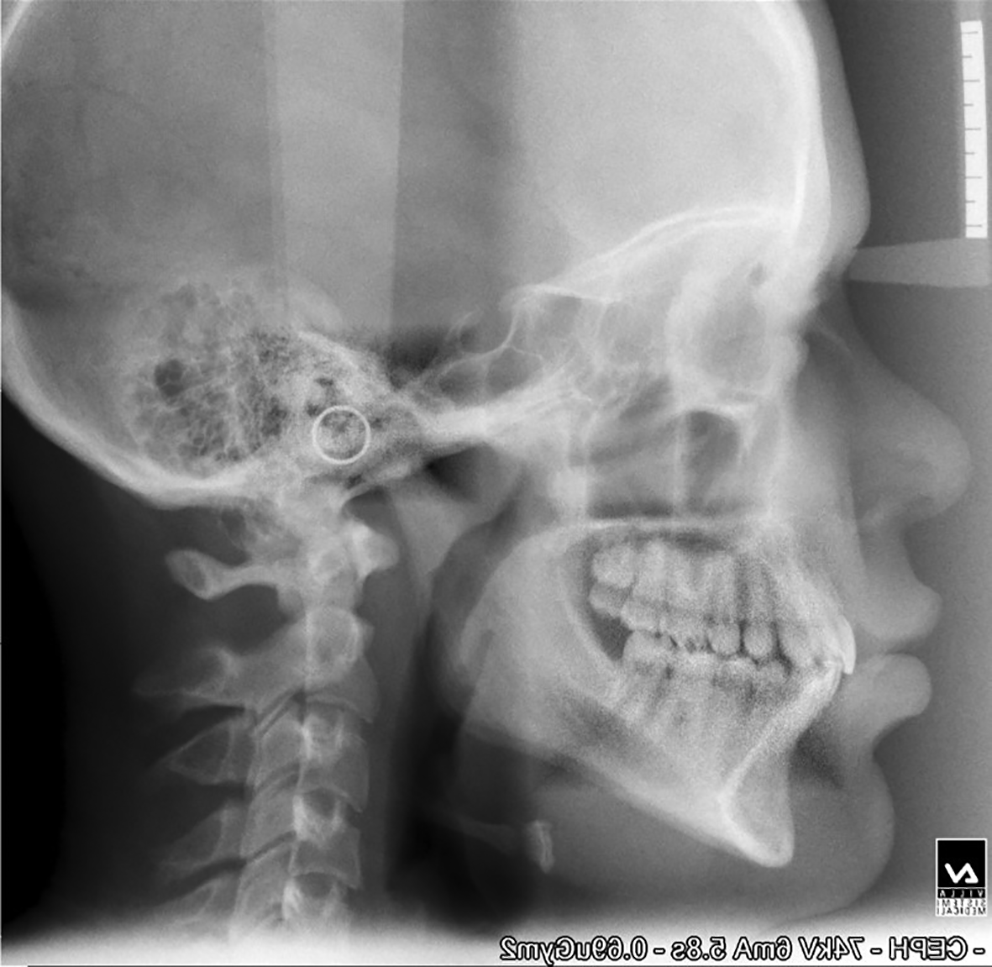

The mean age of the patients at the start of treatment was 12 years. Pre-and post-treatment lateral cephalograms were taken and evaluated for skeletal, dental, and soft tissue changes after wearing a twin block appliance therapy for nine months. Cephalometric changes during treatment are shown in Table 1. Figure 1 shows pre-treatment cephalograms, Figure 2 shows post-treatment cephalograms and Figure 3 shows the superimposition of pre-and post-treatment average digitizations. Twin block appliance wearing resulted in rapid skeletal correction as was evident from a statically significant decrease in angle Point A-Nasion-Point B (ANB), from 7.07±1.98 to 3.33±1.23 degrees (P=0.02); the angle of convexity decreased significantly from 9.87±1.5 to 5.13±1.24 degrees (P=0.01). There was a significant change in Wits appraisal, which decreased from 4.87±0.91 to 3.33±0.72 mm (P=0.04). Angle between Sella-Nasion-Point B (SNB) increased significantly from 74.0±1.46 to 77.9±0.77 degrees (P=0.02). There was a non-significant increase in mandibular length from 86.73±3.34 to 87.8±3.32 mm (P=0.1). The total anterior facial height (increased from 101.73±2.86 to 102.13±2.5 mm, P=0.09) and posterior facial height (increased from 57.27±1.53 to 57.40±1.68 mm, P=0.43) did not show significant changes with no significant increase in Frankfort mandibular angle (FMA increased from 30.73±1.48 to 30.80±1.37 degrees, P=0.67); there were no significant changes in Jarback ratio too (63.73±1.71 to 63.20±1.6, P=0.15); the angle between Sella-Nasion and Gonion-Gnathion (SN-Go-Gn) increased non-significantly from 132.27±2.43 to 132.60±2.29 degrees (P=0.67); the Y-axis increased non-significantly from 56.66±1.75 to 56.86±1.95 degrees (P=0.32). The upper incisor inclination decreased non-significantly from 5.60±1.24 to 4.20±0.86 degrees, (P=0.31) and the lower incisor increased non-significantly from 100.13±2.23 to 101.80±1.37 degrees, (P=0.08). The nasolabial angle increased by 3.8 degrees and the change was statistically significant (P=0.04). The mean pretreatment (stage 0) value of overjet was 9.60±1.35 mm which was statistically significantly (P=0.01) reduced to 3.6±0.91 mm at 9 months (stage IV) of the twin block therapy. The mean overbite before the start of treatment (stage 0) was 6±0.92 mm. This changed to 2.47±0.83 mm at 9 months of twin block therapy. The change was statistically significant (P=0.03).

a4d3a120-46fb-4337-9a75-bc612f9f9675_figure1.gif

Figure 1. Pre-treatment cephalogram.